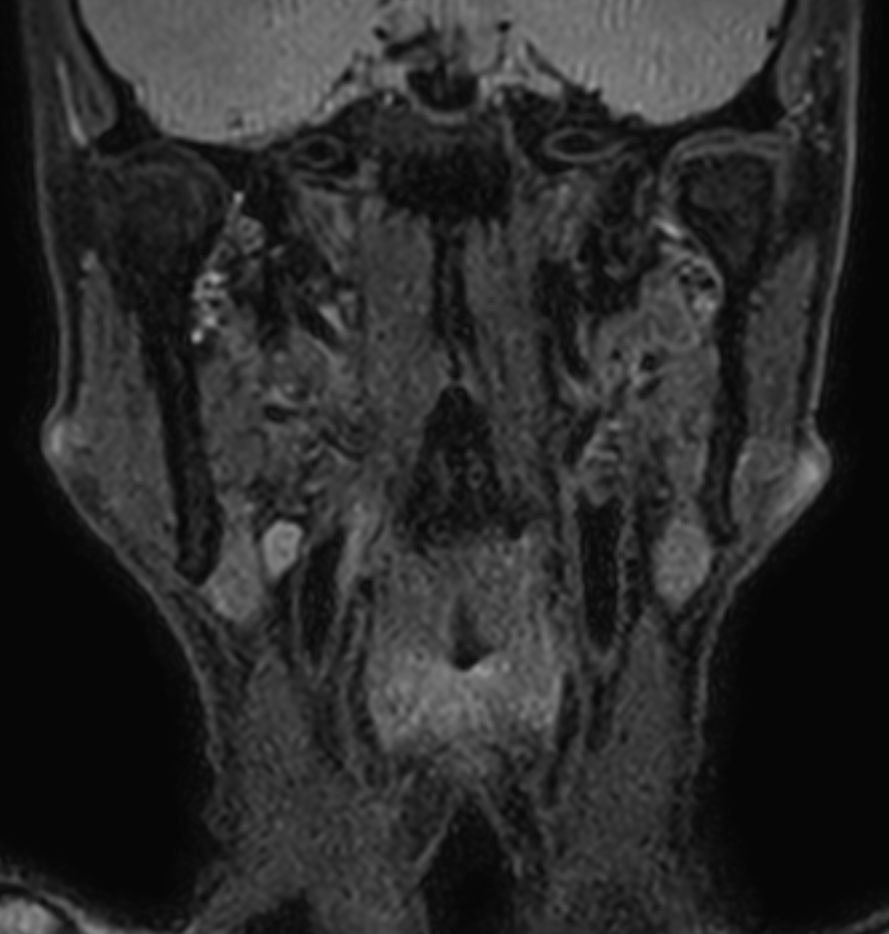

3D T2w TSE Black Blood - Compressed SENSE